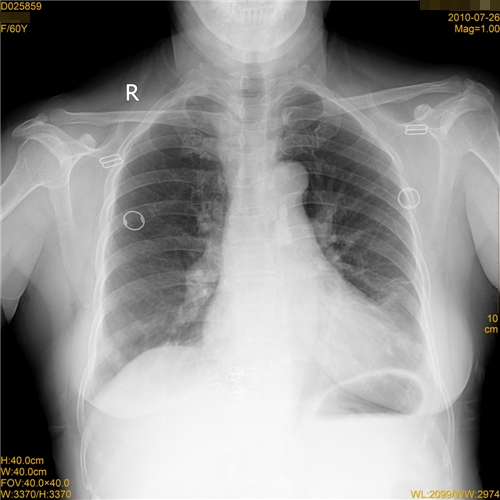

标题: CT27988:胸片容易漏诊啊 [打印本页]

标题: CT27988:胸片容易漏诊啊

女,60岁,胸痛就诊,右肺结核?炎症?其它?(胸片右侧中上肺野确实看不到什么啊)

考虑右侧胸膜炎,右侧炎症。